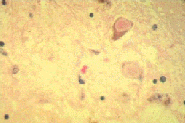

Lewy bodies are often a cellular symptom of Parkinson's Disease and some other neurological disorders.

For more information go to Lewy body. Lewy bodies are basically rubbish bins that get rid of  damaged elements from brain cells. However, Lewy bodies are also detected in the brains of about 10% of people over the age of 60 that do not have Parkinson's Disease or any other neurological disorder. When Lewy bodies are found in normal individuals, the process is sometimes referred to as incidental Lewy body disease (iLBD). The distribution of Lewy bodies in healthy individuals is similar to that found in people with Parkinson's Disease.

It remained unknown as to whether Lewy bodies under these circumstances were merely part of ageing, or indicated that somebody was going to develop Parkinson's Disease. Researchers findings suggest that Lewy bodies in healthy individuals (iLBD) is preclinical Parkinson's Disease and that the lack of symptoms in these people is solely due to the threshold for symptoms not quite being reached. Along with other studies, this means that virtually all symptoms, cellular and physical, are occurring and developing well before it is realised that somebody has Parkinson's Disease, and that cell damage is already taking place before diagnosis.